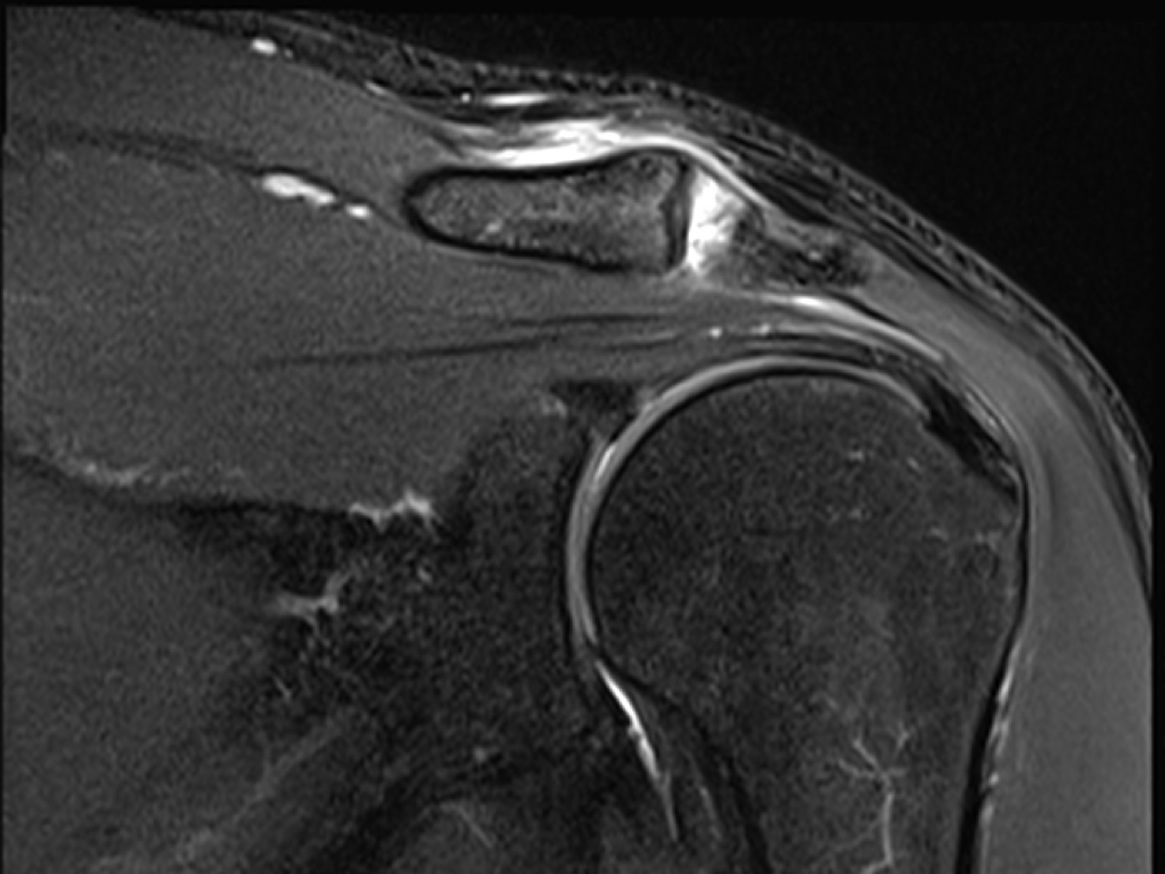

• MRI correlation